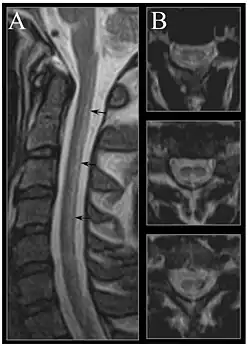

| Image of the cervical spinal cord in vitamin B12 deficiency showing subacute combined degeneration. (A) The midsagittal T2-weighted image shows linear hyperintensity in the posterior portion of the cervical tract of the spinal cord (black arrows). (B) Axial T2-weighted images reveal the selective involvement of the posterior columns. | |

MRI of the brain may show periventricular white matter abnormalities. MRI of the spinal cord may show linear hyperintensity in the posterior portion of the cervical tract of the spinal cord, with selective involvement of the posterior columns.